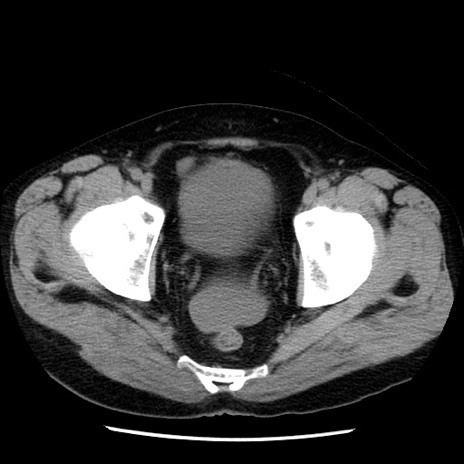

症例29(横断像)

【症例】40歳代男性

【現病歴】2日前から胃痛あり。徐々に周期的な激痛に変化した。本日になっても激痛があるため受診。

【身体所見】意識清明、BT 38-39℃台あり、腹部:膨満、やや硬、右下腹部に圧痛あり。

【データ】WBC 8500、CRP 23.26